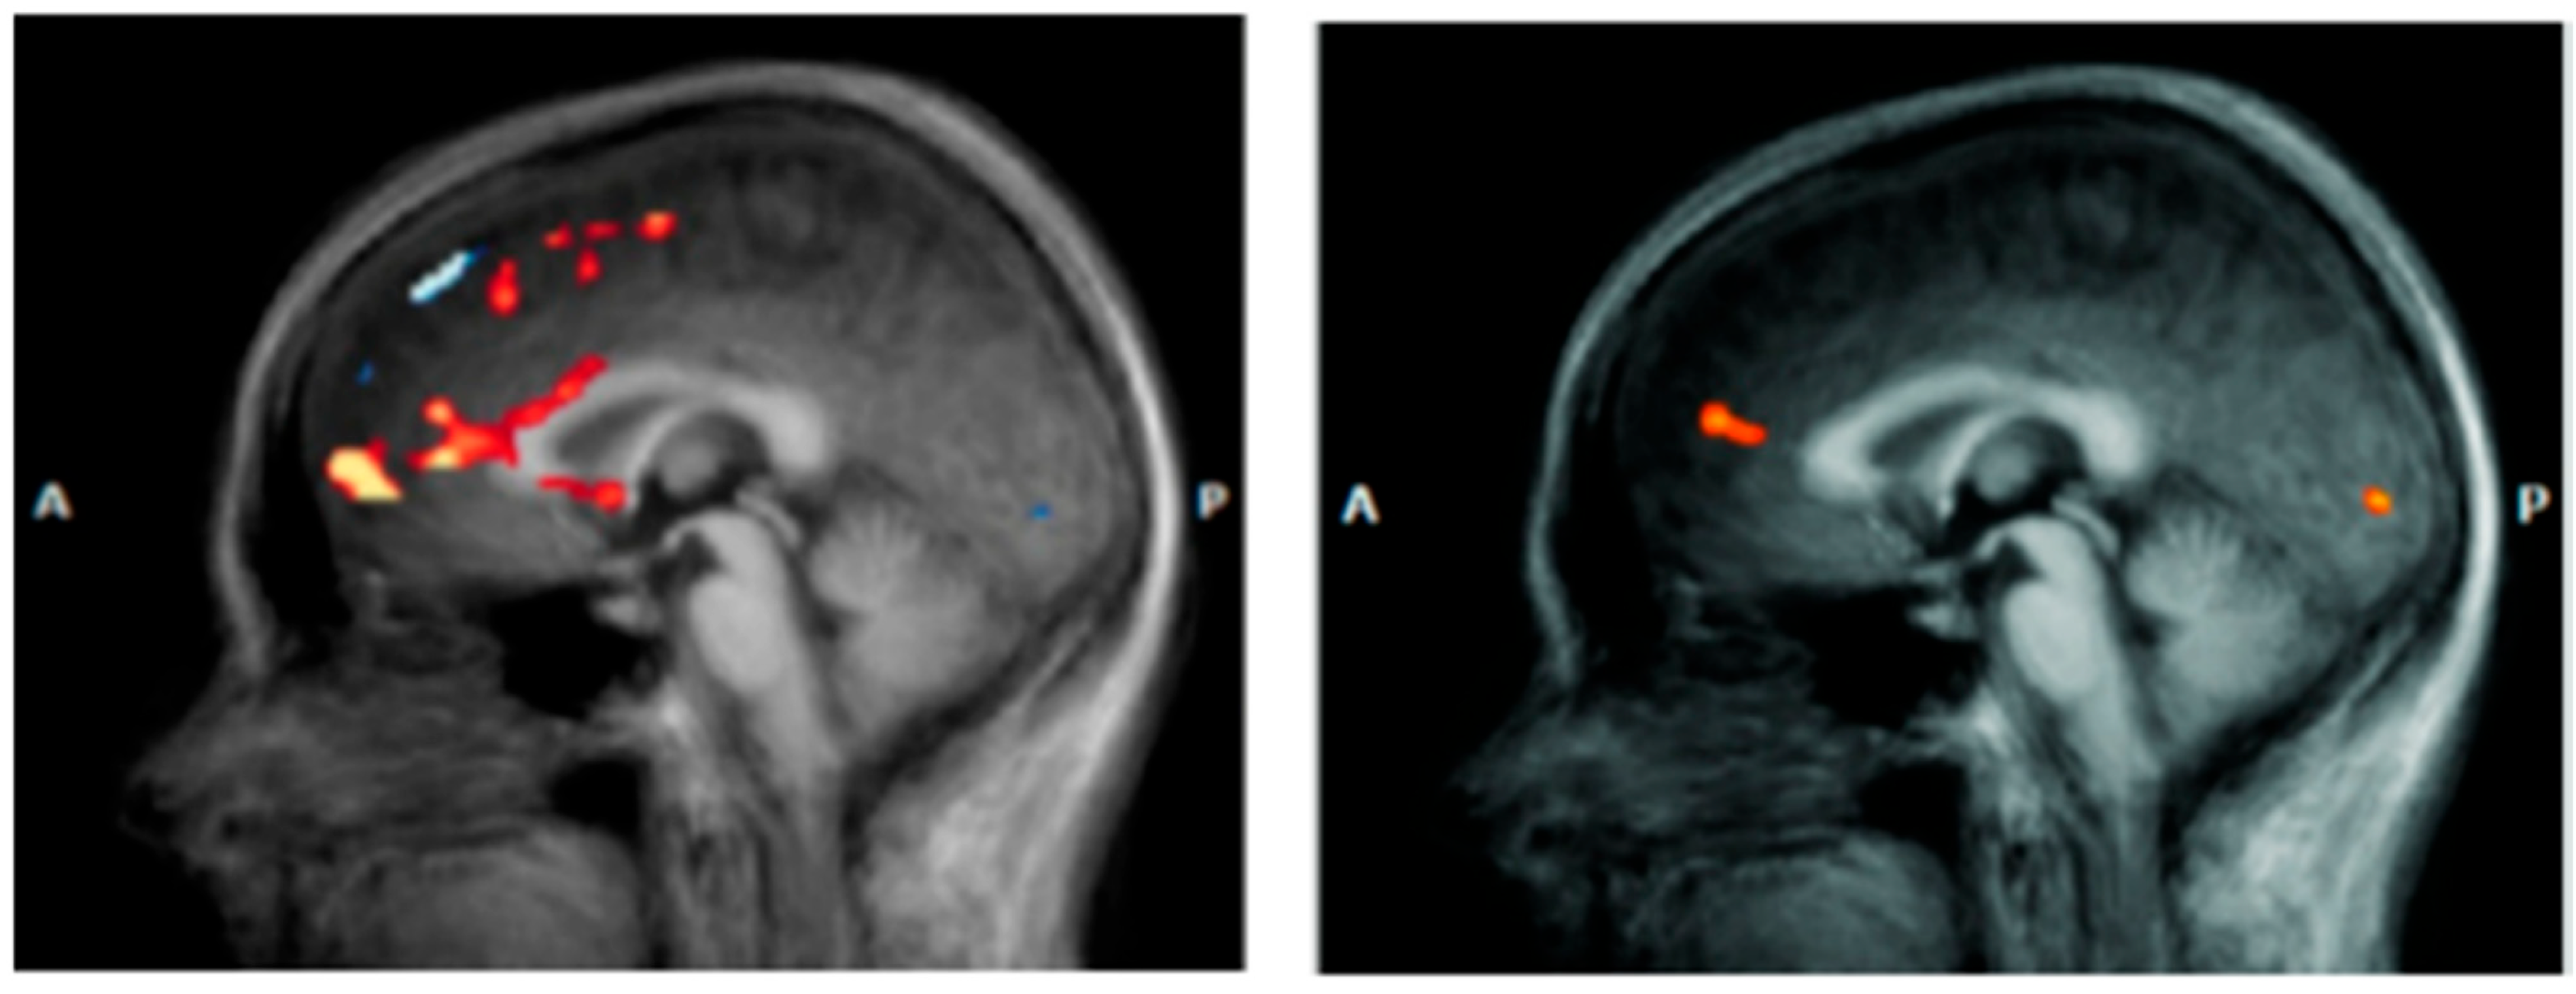

Anterior Cingulate Cortex (ACC). The anterior cingulate cortex (ACC) represents a crucial neural interface between cognition and emotion, playing fundamental integrative roles in conflict monitoring, attention regulation, and emotional response control [74]. In DS, the ACC demonstrates specific functional alterations with direct implications for both pathophysiological understanding and therapeutic response prediction (Figure 4). The ACC can be functionally subdivided into distinct regions that show different alteration patterns in depression. The subgenual portion (sgACC) demonstrates characteristic metabolic hyperactivation, with 20–40% increases in glucose uptake that correlate positively with depressive symptom severity [75]. This hyperactivation represents a robust biological marker of depressive state and has proven valuable for understanding treatment mechanisms and predicting therapeutic responses. The dorsal anterior cingulate cortex (dACC) presents a complementary hypoactivation pattern, particularly evident during tasks requiring cognitive control and conflict resolution [76]. Functional neuroimaging studies document 25–35% activation reductions during Stroop paradigms and executive control tasks, correlating with attentional deficits and executive function compromises characteristic of DS. The sgACC’s extensive anatomical connections with limbic structures, paralimbic regions, and brainstem nuclei involved in mood regulation undergo profound alterations in DS [10]. Anomalous functional connectivity increases between sgACC and amygdala contribute to negative emotional response amplification, while disrupted connectivity with prefrontal regions compromises cognitive control mechanisms (Table 1).

Figure 4.

Anterior cingulate cortex (ACC) in a patient with DS (left) vs. a healthy subject (right) [77].